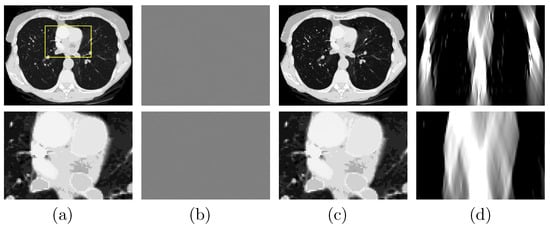

A study is performed to first verify that (1) the DDD algorithm can invert the non-linear model in Equation (3) and numerically accurately recover the basis sinogram from noiseless low- and high-kVp data of the chest phantom acquired with the FAR scan of ; and (2) the DTV algorithm developed and tailored can reconstruct numerically accurate basis images and VMIs from noiseless basis sinogram. In Figure 3a, we display the VMI at 100 keV [], along with a zoomed-in view, and show in Figure 3b their differences from the truth counterparts in Figure 2c (top row). The result confirms that the two-step method can yield accurate reconstructions from noiseless FAR data. In an attempt to demonstrate possible LAR artifacts associated with the phantom, we apply both the DTV and FBP algorithms to reconstructing images from noiseless basis sinogram acquired with a SA scan of LAR , and display them in Figure 3c,d, respectively. It can be observed that the two-step method can significantly reduce the LAR artifacts observed in the FBP image.

Figure 3.

Row 1: (a) VMI of the chest phantom at 100 keV obtained with the two-step method from FAR data, (b) difference between the VMI in (a) and its truth in Figure 2c, and VMIs at 100 keV obtained with (c) the two-step method and (d) the FBP algorithm from noiseless data acquired over a SA of LAR ; Row 2: zoomed-in views of their corresponding images in row 1. The zoomed-in area is enclosed by the rectangular box depicted in the VMI in (a). Display windows [0, 0.22] cm for columns (a,c,d), and [] cm for column (b).

Next, we repeat the studies in Section 3.2 with the suitcase phantom. We show in Figure 8a the VMI and its zoomed-in view reconstructed from FAR data and in Figure 8b their differences from the truth counterparts in Figure 2c (bottom row). The result again confirms the reconstruction accuracy of the two-step method using the suitcase phantom, which is of different complexity and structure to the chest phantom. To reveal the LAR artifacts associated with the suitcase phantom, we apply the DTV and FBP algorithms to reconstruct images from noiseless basis sinogram over an SA of and display them in Figure 8c,d, respectively. It can be observed that the LAR artifacts in the FBP image are almost eliminated in the image reconstructed by use of the two-step method.

Figure 8.

Row 1: (a) VMI of the suitcase phantom at 40 keV obtained with the two-step method from FAR data, (b) difference between the VMI in (a) and its truth in Figure 2c, VMIs at 40 keV obtained with (c) the two-step method and (d) the FBP algorithm from data acquired over a SA of LAR ; and row 2: zoomed-in views of their corresponding images in row 1. The zoomed-in area is enclosed by the rectangular box depicted in the VMI in (a). Display windows [0.1, 0.65] cm for columns (a,c,d), and [] cm for column (b).